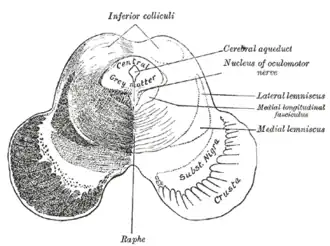

Transverse section of mid-brain at level of inferior colliculi | |